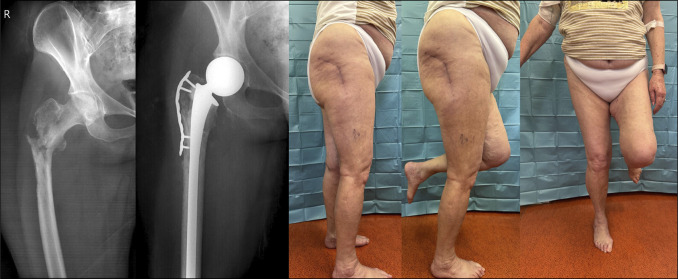

Background: The incidence of metastatic cancer continues to increase, becoming a prevalent condition in oncology orthopaedic practice. The proximal femur is the third most common site of skeletal metastases. Two possible options for endoprosthetic reconstruction of proximal femur metastasis include proximal femur resection and replacement with megaprosthesis and hemiarthroplasty with a long-cemented revision stem.

Methods: To facilitate better decision making, we conducted a retrospective study comparing these alternatives. This is a single-institution, retrospective, observational study. Patients with metastatic disease of proximal femur who had a reconstruction with either a proximal femoral replacement (group A, 27 patients) or reconstruction using a hemiarthroplasty with long revision cemented stem (group B, 31 patients) were included for analysis.

Abstract Image